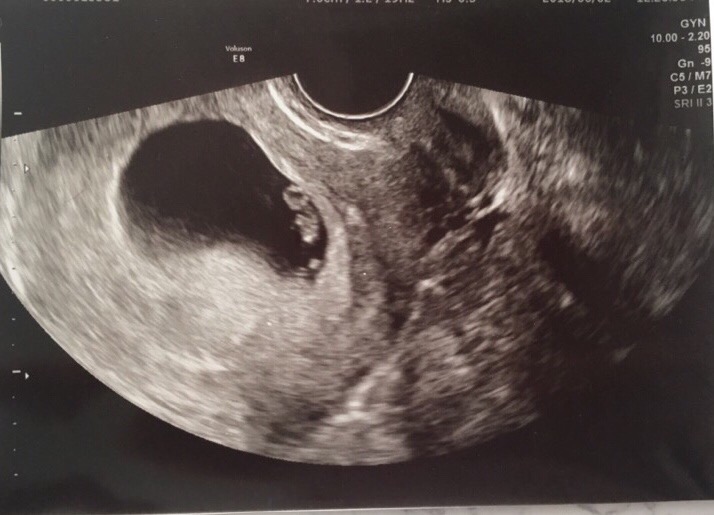

임신9주 : 젤리곰 만나다, 임산부 방광염(?)

임신9주 : 젤리곰 만나다, 임산부 방광염(?) 원래 병원에서 다음 검진은 12주에 오라고 했지만, 9-10주 사...